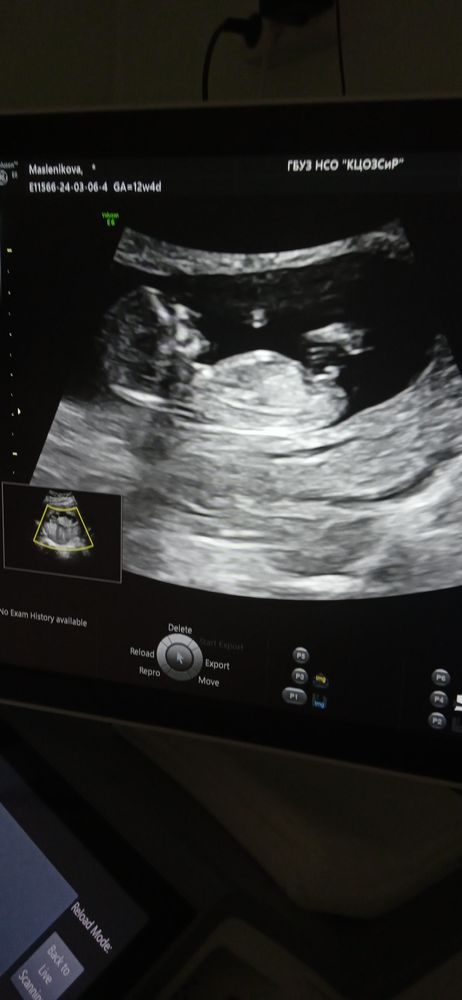

Не хватает терпения у меня, сегодня была на 1-ом скрининге, срок 12.5 , сказали чуть ли не железно, что мальчик.

Может кто разбирается, кого видно подскажите пожалуйста🙏🙏

Ну у девочек на УЗИ пипка параллельно позвоночнику должна быть, а у мальчиков перпендикулярно... А где ваш снимок УЗИ?

Кристина Сергеевна, похоже и правда мальчик, там же ещё машонку уже можно рассмотреть... Но на, втором УЗИ точно скажут)..

Через недельку-другую точно можно будет увидеть, но действительно очень похоже на мальчика.

Вот мой снимок, в комментариях прикрепляла)